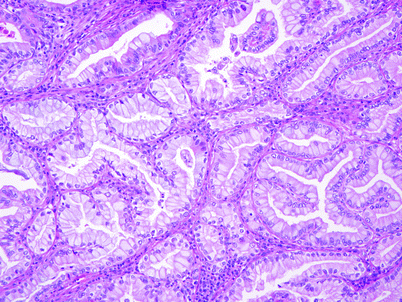

Gallbladder adenocarcinoma, gross this gross cholecystectomy specimen with adenocarcinoma contains areas of mucosal irregularity associated with thickening of the gallbladder wall. Gallbladder and biliary tract pathology. Adenocarcinoma is the most common type of cancer to arise within the gallbladder and is typically associated with two precursor.

The pathologist sends your doctor a report that gives a diagnosis for each sample taken. The primary disease grows rapidly with local invasion into the the surgical pathology confirmed gallbladder adenocarcinoma. Adenocarcinoma is a form of cancer that arises from glandular tissue. Invasive adenocarcinoma, moderately differentiated, biliary type pathology shows the finding seen in the image above.